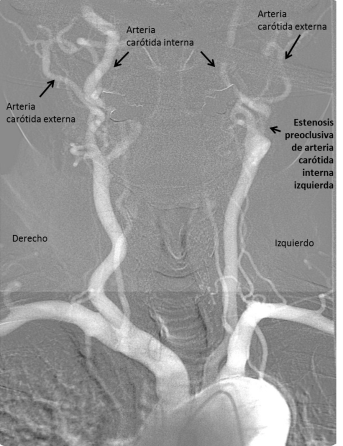

En la Imagen 2 se señalan ambas arterias carótidas internas y externas. Se diferencian en esta proyección porque la arteria carótida interna cervical no da ninguna rama. Si observamos en el lado derecho el calibre de la arteria carótida interna es mucho mayor que el de la externa mientras que en el lado izquierdo el calibre es similar. Este dato angiográfico es sugestivo de estenosis preoclusiva.